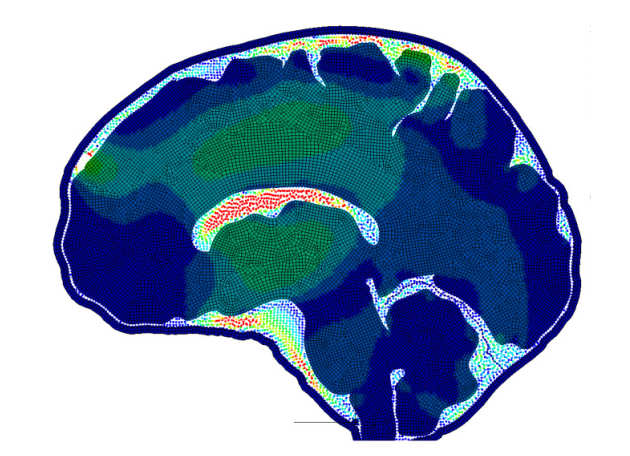

The cerebrospinal fluid (CSF) is one of the most challenging features to represent correctly in a finite element model of the head and brain. Currently, most models employ a solid element, Lagrangian mesh representation of the CSF, achieving fluid-like responses by using low shear and bulk moduli. The small space which the CSF occupies, in addition to the large relative displacement of the brain to the skull, means the Lagrangian mesh method is not well suited for this situation. This study investigates the usefulness of a particle method, Smoothed Particle Hydrodynamics (SPH), in representing the CSF in the brain. We hope to allow greater accuracy in modelling injuries which have direct relation to the relative movements of the brain, such as subdural hemorrhaging, coup and contrecoup, and chronic traumatic encephalopathy.

The cerebrospinal fluid (CSF) is one of the most challenging features to represent correctly in a finite element model of the head and brain. Currently, most models employ a solid element, Lagrangian mesh representation of the CSF, achieving fluid-like responses by using low shear and bulk moduli. The small space which the CSF occupies, in addition to the large relative displacement of the brain to the skull, means the Lagrangian mesh method is not well suited for this situation. This study investigates the usefulness of a particle method, Smoothed Particle Hydrodynamics (SPH), in representing the CSF in the brain. We hope to allow greater accuracy in modelling injuries which have direct relation to the relative movements of the brain, such as subdural hemorrhaging, coup and contrecoup, and chronic traumatic encephalopathy.